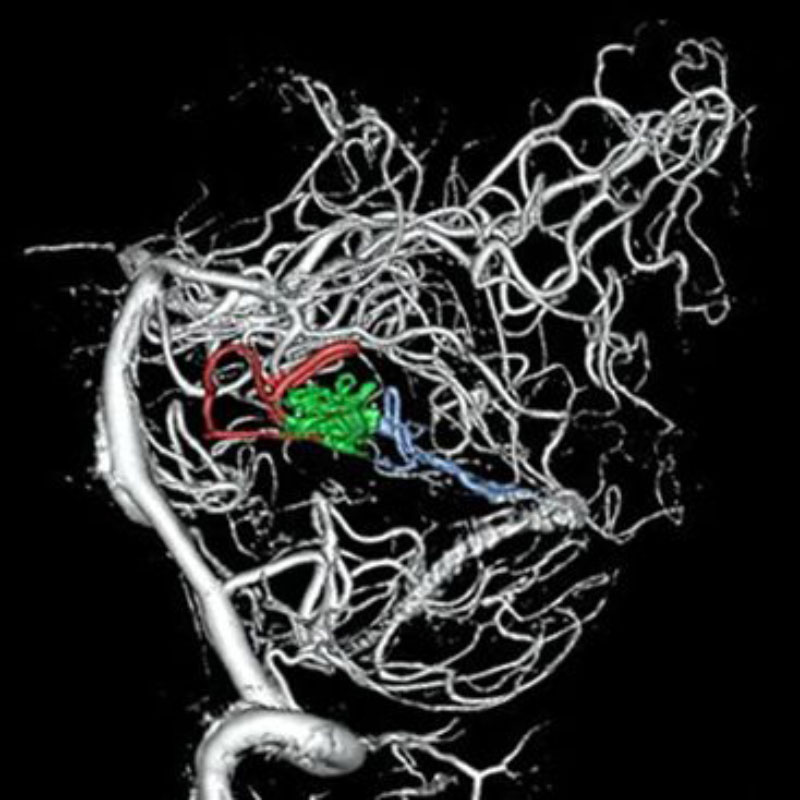

No.359 モニタリング

No.359 手術前

No.359 手術中

No.359 手術後

出血既往があり。2回の手術前血管内手術の後に、

Lateral transpeduncular approachにより再々出血予防を目的に

摘出手術を行う。完全摘出であることを確認した。

手術による合併症や後遺症なしで退院した。経過良好。